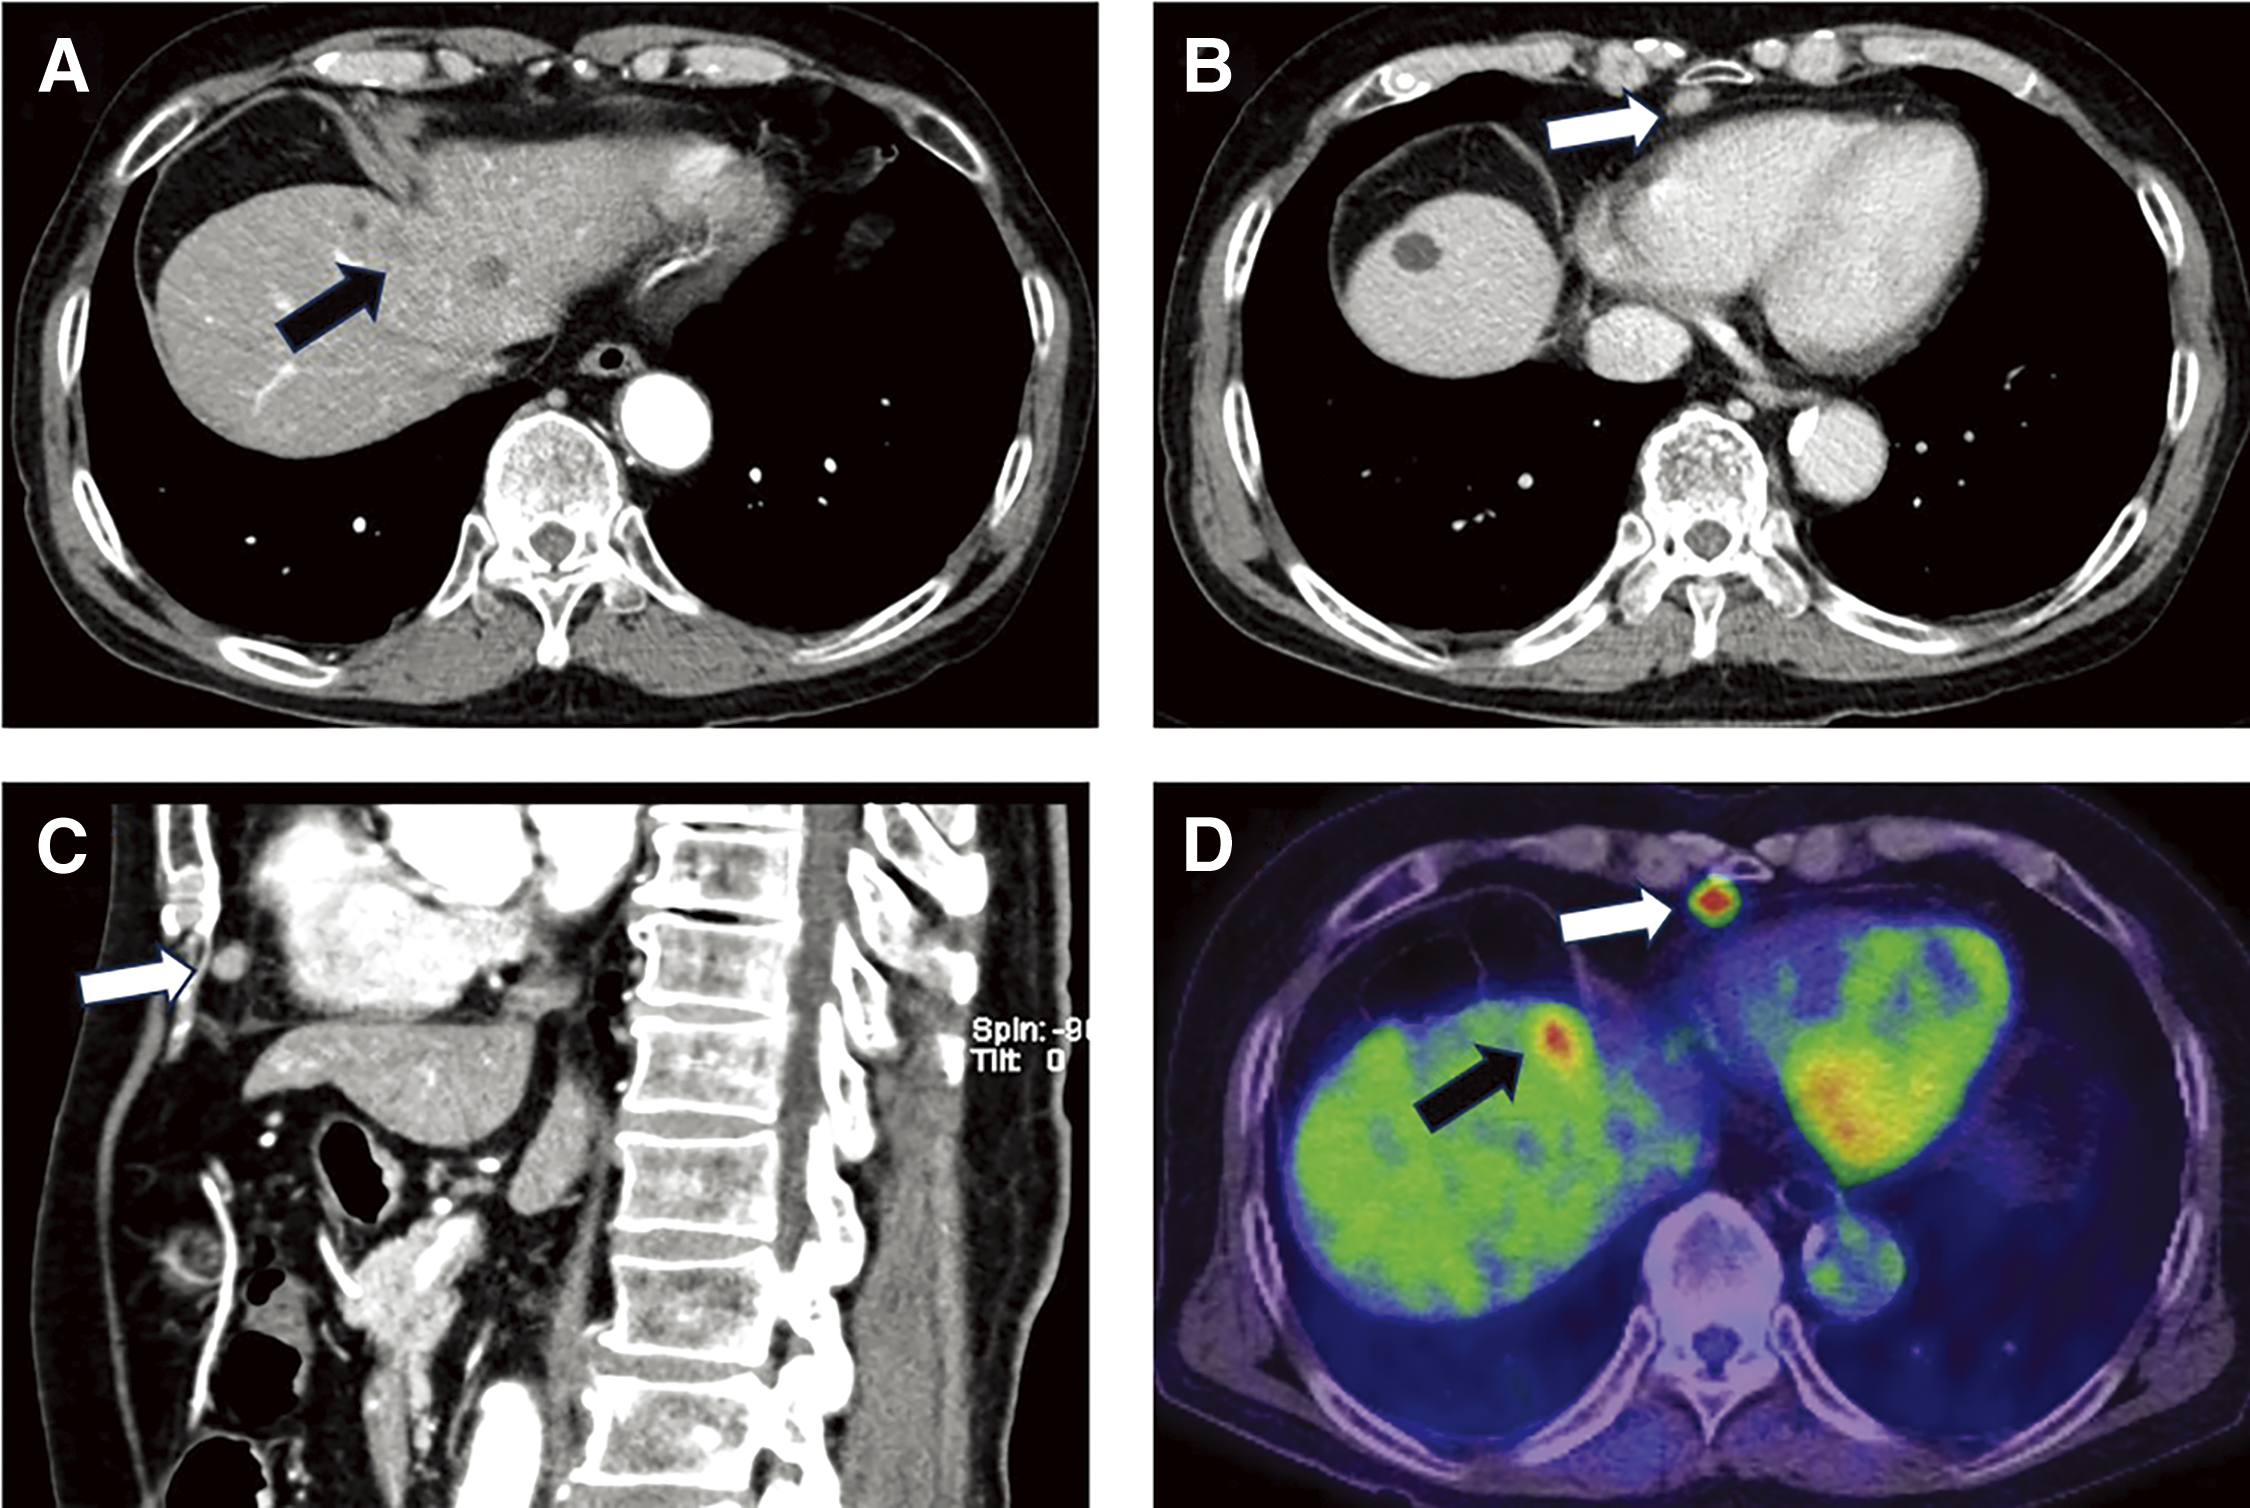

The patient is a 74-year-old man who had surgery for cervical esophageal cancer 2 years ago. The final diagnosis was moderately differentiated squamous cell carcinoma (SCC) with LN metastasis, pT3N1M0 pStage III. Chemoradiotherapy was performed and there was no recurrence of the esophageal cancer. During follow-up, a low-density lesion, a diameter of 15 mm, was detected in segment 4 of the liver by CT (Fig. 1A). The tumor was located just adjacent to the umbilical portion. There were some swollen LNs in the anterior mediastinum (Figs. 1B and 1C). The accumulation of FDG was also detected in the hepatic lesion (standardized uptake value; SUVmax: 8.4) and the anterior mediastinal LN (SUVmax: 11.1) by PET (Fig. 1D). Needle biopsy was performed for the liver tumor and the diagnosis was ICC (Figs. 2A and 2B). The elevation of the serum level of carbohydrate antigen 19-9 (CA19-9) was detected and its level was 119 ng/mL. The levels of carcinoembryonic antigen (CEA) and SCC were within normal range. To confirm the diagnosis of the swollen LNs in the anterior mediastinum, an excisional biopsy was performed. In the operation, there were several firm LNs pulpable just behind the sternum. According to the pathological findings, the tumor in the LN was an intermediate differentiated adenocarcinoma. Atypical cells with increased nuclear chromatin and enlarged nuclei were proliferating and forming glandular structures (Figs. 2C and 2D). The structure of the tumor in the LN was similar to that of the hepatic lesion. Immunohistochemistry showed that the tumor was positive for CK7 and CK20, weakly positive for MUC5AC, but negative for CDX-2, Napsin, TTF-1, and p40 (Fig. 3). The final diagnosis was the lymphatic metastasis from ICC. As the diagnosis of distant metastasis (Stage IVB), the chemotherapy using Gemcitabine, Cisplatin, and Durvalumab was performed for 8 courses. The new lesion appeared just next to the main tumor in S4 (Fig. 4) and the elevation of CA19-9 was also observed (Fig. 5). We could not detect any swollen LNs in the anterior mediastinum by PET or CT. In addition, it was difficult to continue the chemotherapy due to the renal dysfunction. As the tumors were located in the left lobe of the liver, a left hepatectomy with LN dissection was performed. In the operation, there were multiple intrahepatic metastatic lesions limited to the left lobe of the liver. Grossly, the lesion corresponds to a mass-forming type with a central necrotic area and several satellite nodules (Fig. 6). The size of the main tumor was 30 mm in diameter. Most of the tumor cells were viable and they showed serosal and neural invasion around the portal vein (S1, Vp1, Vv0, and Va0). There were no metastases in the regional LNs. Although re-elevation of CA19-9 is observed after hepatectomy (Fig. 5), the patient does not have any recurrence for 9 months after hepatectomy.

Fig. 1

Contrast-enhanced CT and FDG-PET. (A) CT showed a 15-mm-large, low-density lesion in S4 of the liver. (B) CT demonstrated the enlarged lymph node in the anterior mediastinum (axial view). (C) Anterior mediastinal lymph node (sagittal view). (D) The accumulation of FDG in the lymph node and the hepatic lesion was observed by PET. Black arrow: hepatic lesion; white arrow: metastatic lymph node